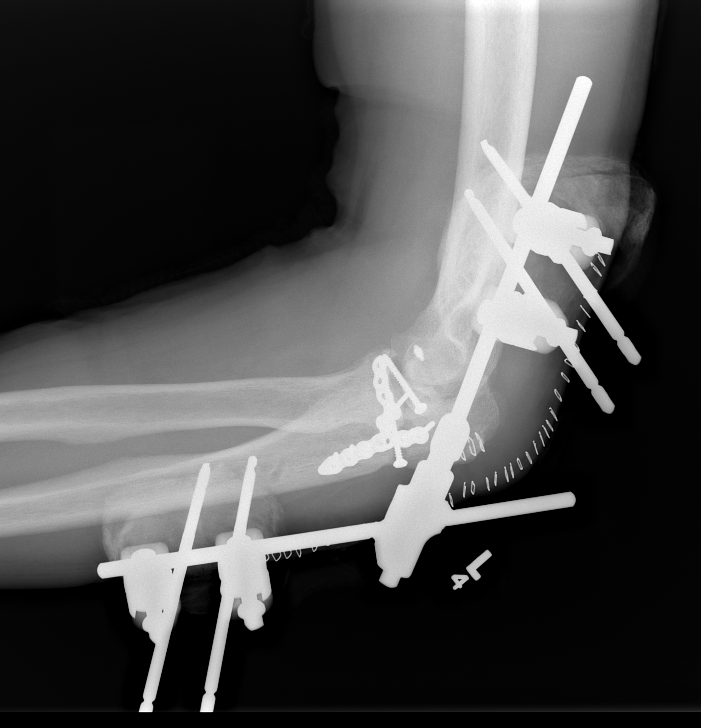

External fixator elbow 1External Fixator Elbow 2

elb ex fixelb ex fix

Compass Hinge Lateral XrayCompass Hinge AP Xray